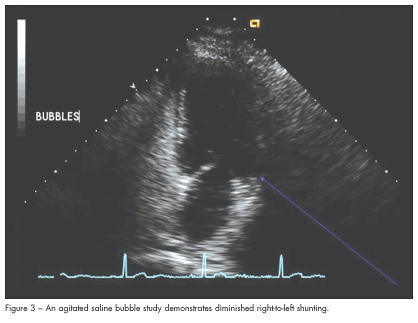

A follow-up 2-dimensional echocardiogram 2 months later demonstrated normalization of RV function. There was a persistent patent foramen ovale, although the degree of right-to-left shunting had decreased significantly (Figure 3).

In massive acute pulmonary embolism, the presence of severe RV dysfunction leads to decreased LV preload and subsequently decreased cardiac output. This patient’s echocardiogram demonstrated moderate RV dysfunction and the presence of a large patent foramen ovale with right-to-left shunting by agitated saline bubble study. The presence of this large right-to-left shunt likely explains his profound and persistent hypoxemia, as well as the lack of hemodynamic instability. This patient’s interatrial septal defect allowed for adequate LV filling by allowing decompression of the right ventricle and shunting of blood into the left ventricle.